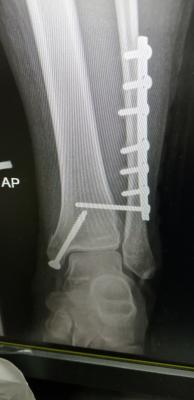

Hey guys, I wonder does anyone have the same experience with me before. I broken my right leg fibula bone and my ankle was fractured last year April and undergo multiple surgeries. I have one plate and some screws on my fibula bone and same on my ankle.

QUOTE(vincabby @ May 10 2019, 09:37 AM) hi. hope the surgery was a success. for the next one month u will need crutches for sure. Once the cast is out, then you can slowly put weight but you won't find a lot of movement till at least 6 months. i am putting it longer so you wont pressure yourself and risk a bad healing period. hey. ya surgery was a success. have one metal bar and 2 screws. I bought the old ppl tongkat. easier to use than crutch. my friend lend me his when he was suffering from knee injury. once I can put some weight, I'll use those crutch. I find it tough to balance on crutches, so I bought old ppl tongkat.

QUOTE(vincabby @ May 10 2019, 02:10 PM) that might not be comfortable in the long run. try the ones where u put your whole arm through the support for the crutch instead of under armpits. those are tiring. if u are using the old man ones, guess u should spend more time sitting and resting. I have both. The old one, and whole arm. I didn't buy under armpits. Unstable and dangerous to use. The old ppl one is for stability. Once my feet can hit the ground, I'll use the whole arm one. My friend lend the whole arm to me while I bought the old ppl one. I don't expect myself to move so much already. Just in bed, and during meals. And some leg day exercise to boost my thigh energy. QUOTE(abuyon @ May 10 2019, 02:13 PM) u might have osteochondral injury of your ankle cartilage..that is y u have bad pain after bad fractured... Mai scare me leg. My scan results are out. Ligament tendon all good. Just bone broken and one part dislocated. Broken part all screws. Dislocated, screwed back to strengthen. Attached thumbnail(s)